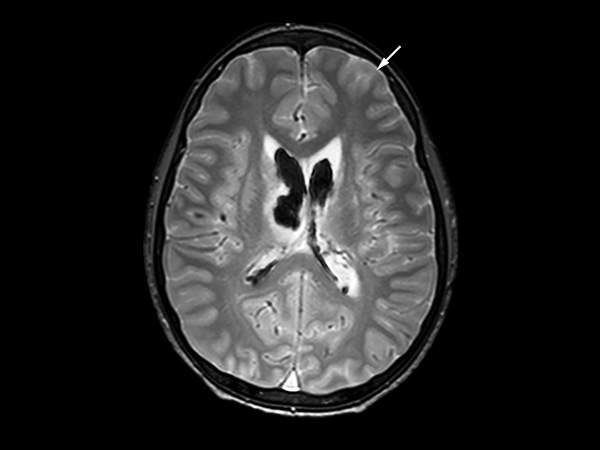

In this case, a 10-year-old girl thrown from a horse. The SWIp images provided increased visibility of the corpus callosum injury compared to the T2-weighted, diffusion weighted and gradient echo images, see the box in the images. SWIp also provides increased visibility of the cortical contusion (arrows) compared to gradient echo imaging. In this case, SWIp helped to characterize the extent of the patient’s injury, which is important to know for short term care and longer term prognosis and rehabilitation.

Axial T2w SSh TSE